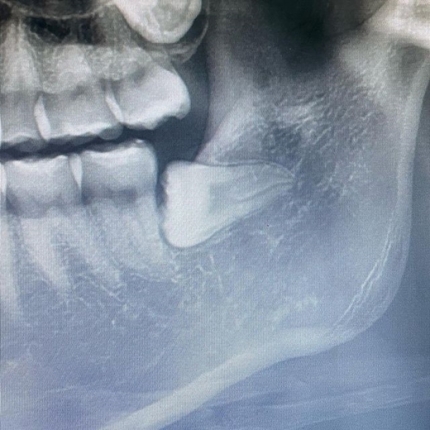

还有截图的照片和评论说“拔智齿肿得像哈姆太郎” , 吸引了人们的视线 。

徐信爱最近说“那天是我初恋结束的日子” , 并上传了拔牙后的照片 , 一时成为话题 。仅凭因拔除智齿而肿胀的脸庞 , 就能猜出手术有多不容易 , 令人担心 。